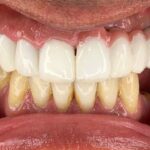

ایمپلنت مجموع قطعاتی است که با جراحی داخل فک ثابت میشوند روی آن دندان مصنوعی قرار میگیرد و در نهایت ظاهری مشابه با دندان طبیعی پیدا میکند.

بهطور کلی برای گذاشتن ایمپلنت دندان چندین مرحله باید انجام شود تا قطعات تشکیل دهنده در کنار یکدیگر قرار گیرند و بیمار بتواند به جای دندان طبیعی از آن استفاده کند. ایمپلنت از نظر ظاهری مشابه دندان طبیعی است و در دهان همان حس طبیعی را برای جویدن القا میکند و سوء هاضمه ایجاد شده بر اثر ناتوانی در جویدن غذا را برطرف مینماید.